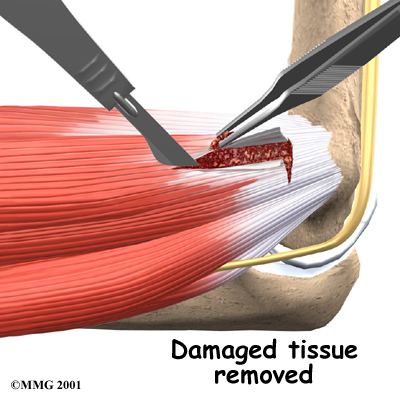

Tendon Debridement

When problems are caused by tendonosis, surgeons may choose to take out (debride) only the affected tissues within the tendon. In these cases, the surgeon cleans up the tendon, removing only the damaged tissue.

The following images show each step:

Tendons Released

Damaged Tissue Removed

Bone Spurs Removed

Tendons Reattached